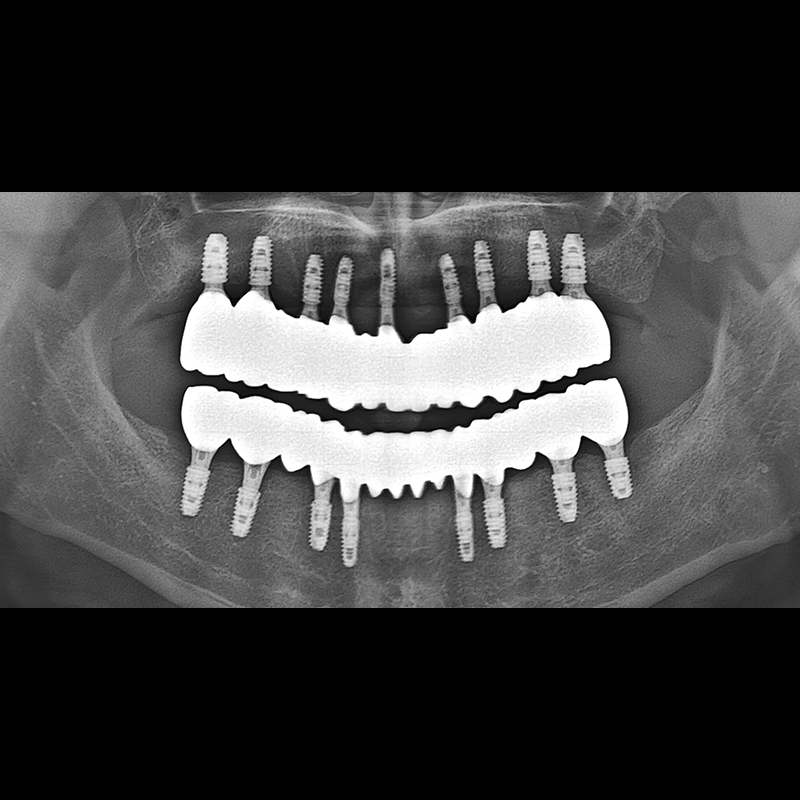

IMPLANT

BEFORE AFTER

임플란트 전후사진 2025.05.30

결손된 치아 부분과 살리기 힘든 치아 위치에 임플란트를 식립하였습니다.